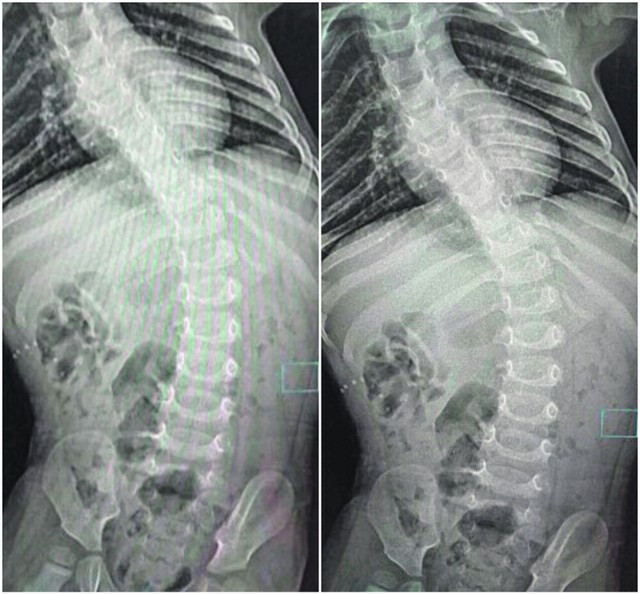

SAKUPLJEN NOVAC Devojčica putuje na intervenciju na kičmi: Operacija u Turskoj jedina nada da MIA PROHODA

Mia Žikić (4) iz Paraćina koja ne može sedi i hoda zbog devijacije kičme, početkom oktobra otići će na operaciju u Tursku, za koju su brojni donatori skupili 50.000 evra, a polovinu za svega 20 dana.

Ova operacija će omogućiti devojčici da živi kao i njeni vršnjaci. Operacija u turskoj klinici Adžibadem košta oko 50.000 evra, a nešto više od polovine nedostajuće sume za svega 20 dana sakupljeno je zahvaljujući akciji “Kilometri za Miju”, koju je pokrenuo Vladan Vugdelija, diplomirani pravnik zaposlen u Javnom preduzeću za podzemnu eksploataciju uglja u Resavici.

Klinika kao dom

Kako je “Blic” pisao, Mia ima četiri godine i veći deo svog života provela je u bolnici. Zbog slabosti mišića koja se javila nakon rođenja došlo je do krivljenja kičme (kifoskolioze) pa za razliku od svojih vršnjaka, ova devojčica ne može ni da sedi sama, a kamo li da potrči. Klinika za rehabilitaciji u Beogradu, sa nepunih godinu dana života, postala joj je maltene novi dom. Devojčica je dobila mider kako bi se stabilizovao trup i ispravio kičmeni stub, a sve kako bi mogla da sedi i da se kreće. Nažalost, nijedan od ovih pokušaja nije bio uspešan pa je jedina opcija koju predlažu lekari – operacija kičme i ugradnja šipke da bi se kičmeni stub ispravio.